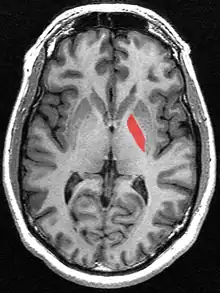

![]() Globus pallidus (in red) shown within the brain | |

The globus pallidus (GP), also known as paleostriatum or dorsal pallidum,[1] is a subcortical structure of the brain. It consists of two adjacent segments, one external, known in rodents simply as the globus pallidus, and one internal, known in rodents as the entopeduncular nucleus. It is part of the telencephalon, but retains close functional ties with the subthalamus in the diencephalon – both of which are part of the extrapyramidal motor system.[2] The globus pallidus is a major component of the basal ganglia, with principal inputs from the striatum, and principal direct outputs to the thalamus and the substantia nigra. The latter is made up of similar neuronal elements, has similar afferents from the striatum, similar projections to the thalamus, and has a similar synaptology. Neither receives direct cortical afferents, and both receive substantial additional inputs from the intralaminar thalamus.

In the primate basal ganglia, the globus pallidus is divided into two parts by the medial medullary lamina. These are the internal globus pallidus (GPi) and the external globus pallidus (GPe); both are composed of closed nuclei surrounded by myelinic walls.